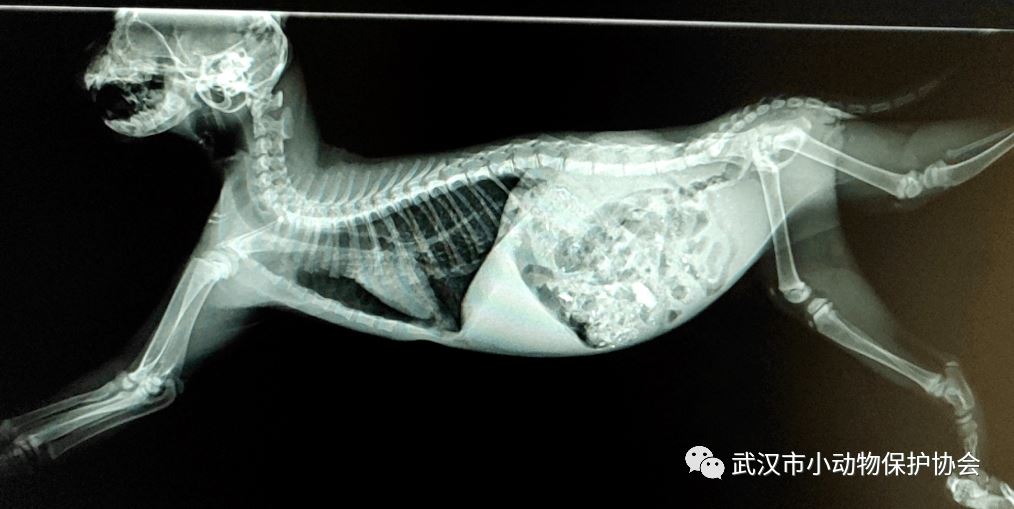

网友在公众号上发了一个视频,在龚家岭收费站一只被撞伤的大黄狗,痛苦的嚎叫着。会长收到消息后,立即前往了现场。狗狗鼻腔和口腔都在吐血,救助后立即送往徐东的医院。

医生检查,它头部有明显的破溃,后腿多处骨折,更棘手的是,它肚子里还有四个宝宝。经过几天的调养,医生给它安排了修复手术,又过了一周,它生下四个宝宝,遗憾的是有两个死胎。凤凰带着宝宝在医院修养了三周后,出院送往基地。

凤凰的医疗费用是 5500元。